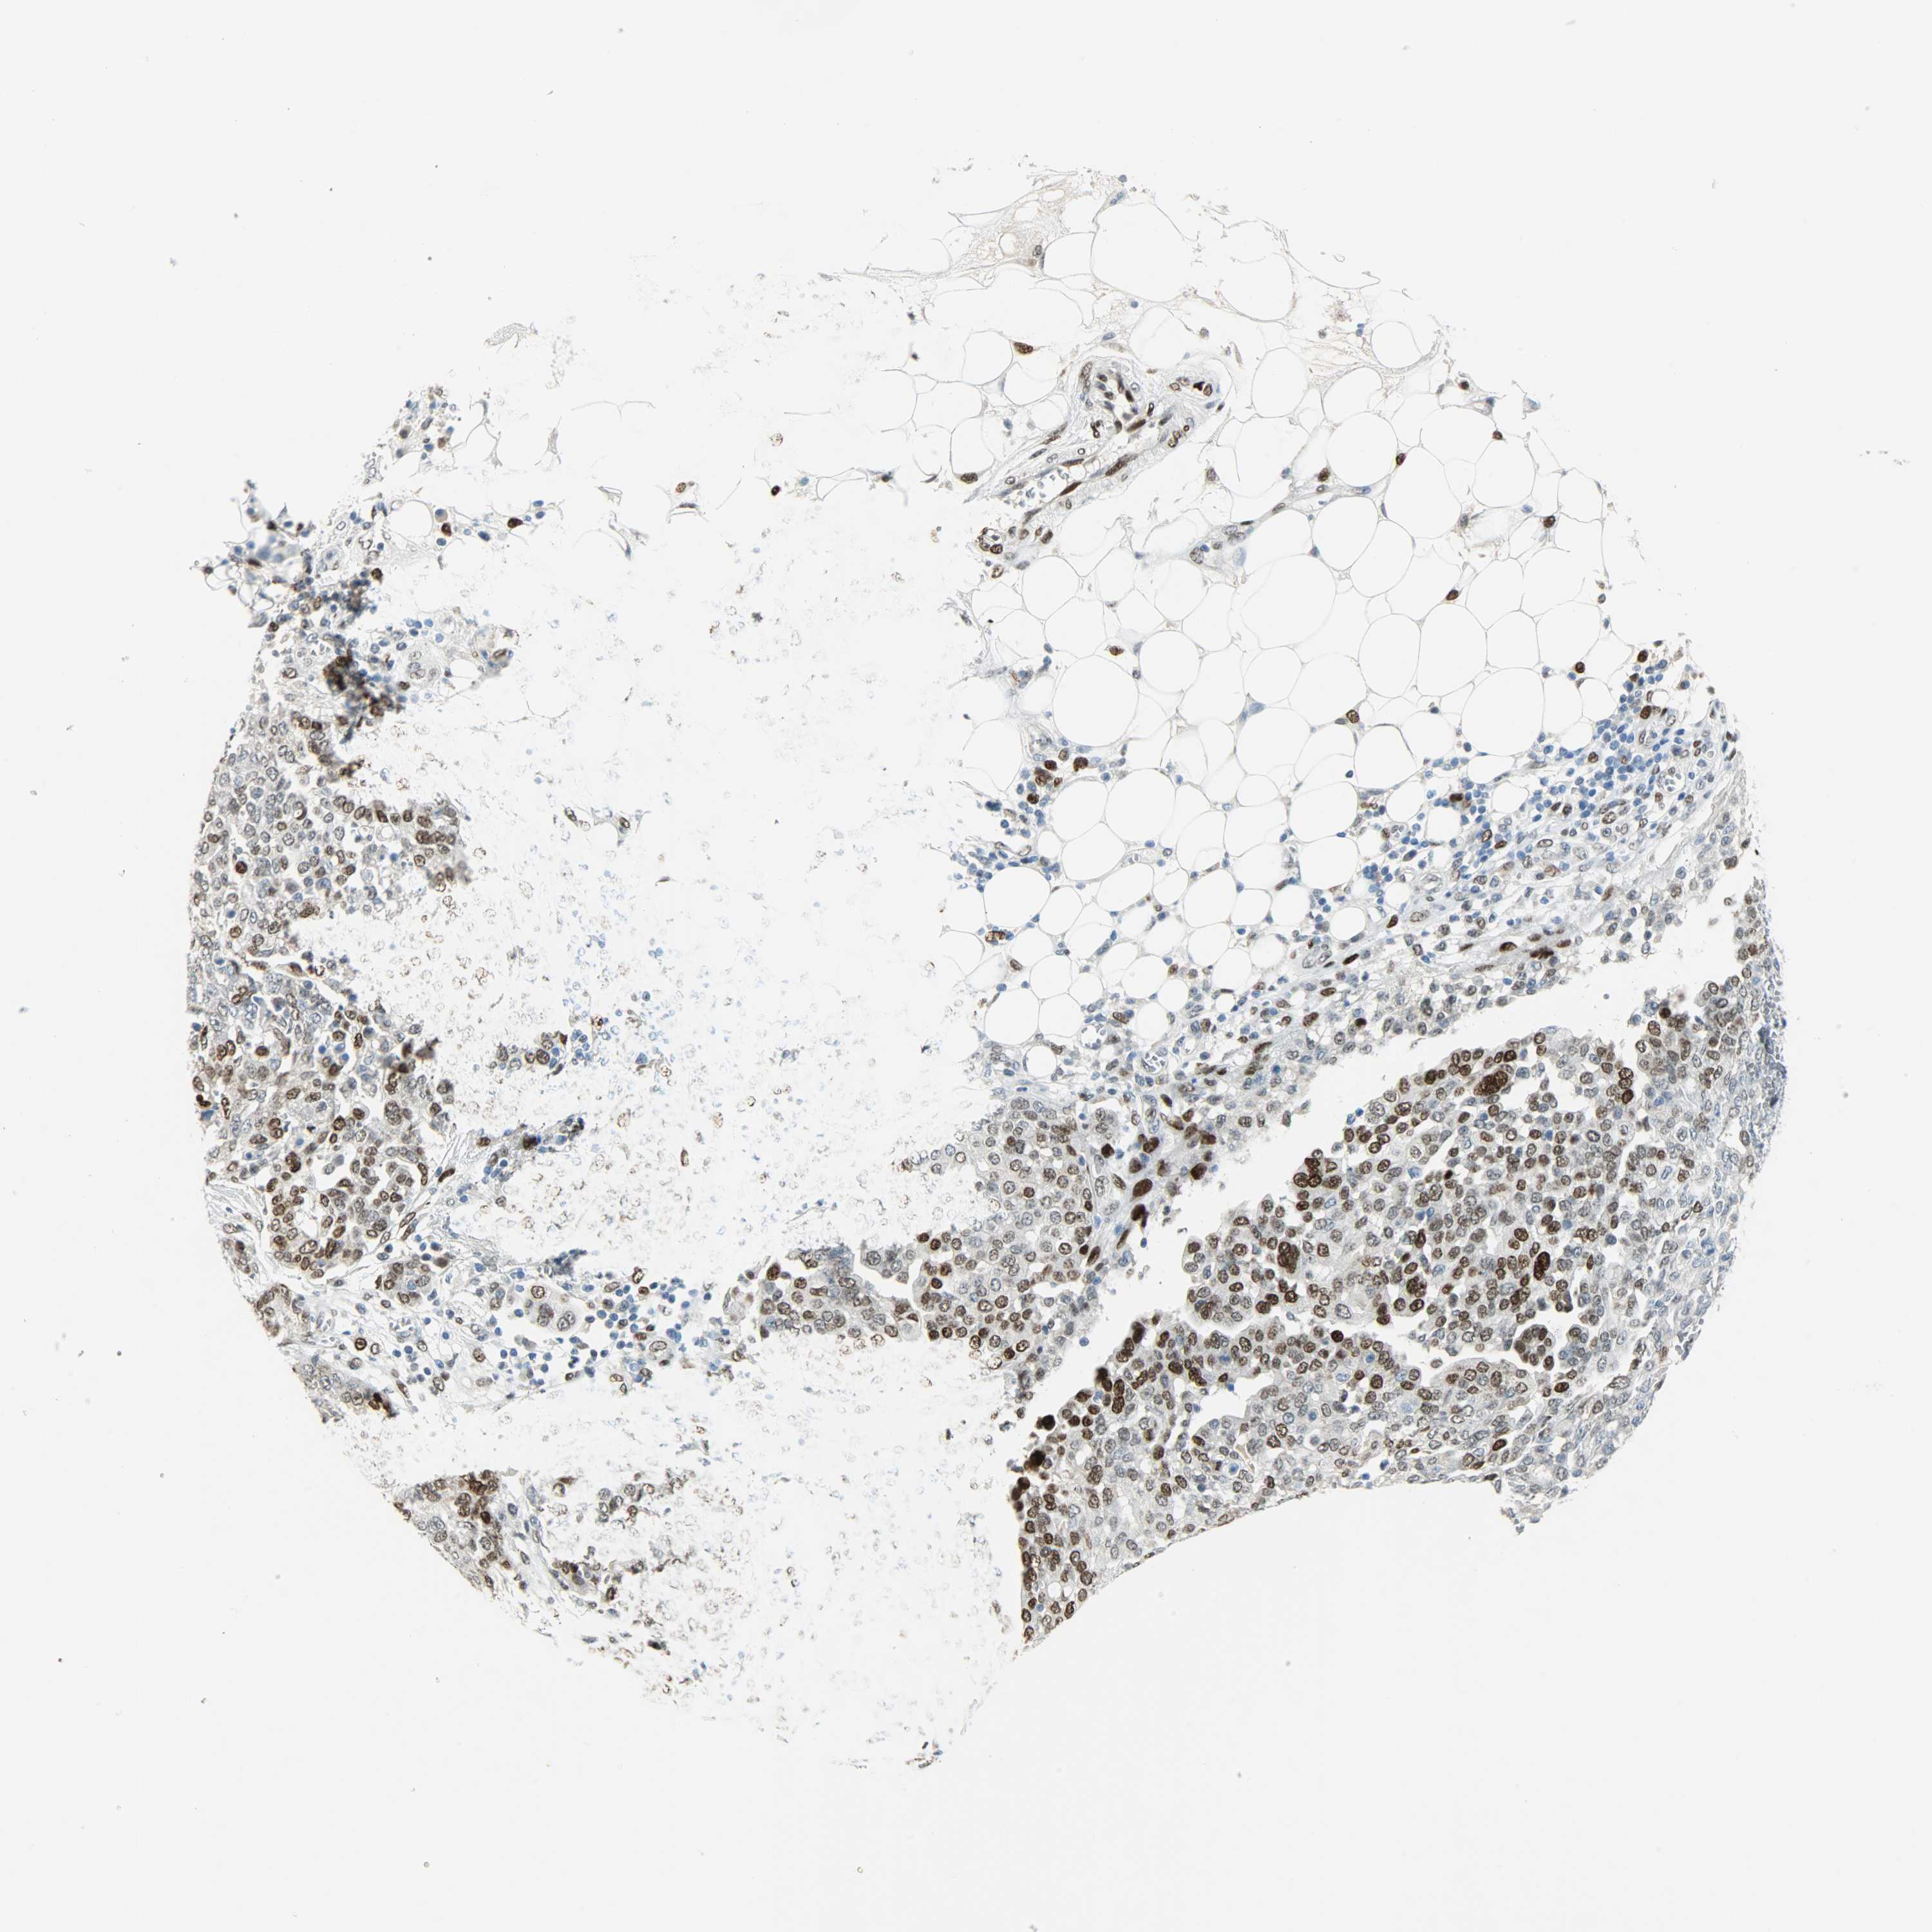

OVARIAN CANCER - Protein expressioni

A mouse-over function shows sample information and annotation data. Click on an image to view it in a full screen mode. Samples can be filtered based on level of antibody staining by selecting one or several of the following categories: high, medium, low and not detected. The assay and annotation is described here.

Note that samples used for immunohistochemistry by the Human Protein Atlas do not correspond to samples in the TCGA dataset.

Antibody stainingi

Antibody staining in the annotated cell types in the current human tissue is reported as not detected, low, medium, or high, based on conventional immunohistochemistry profiling in selected tissues. This score is based on the combination of the staining intensity and fraction of stained cells.

Each image is clickable and will lead to virtual microscopy that enables deeper exploration of all samples and also displays staining intensity scores, fraction scores and subcellular localization as well as patient and tissue information for each sample.

Antibody HPA019149

Antibody CAB004464

Staining

High

Medium

Low

Not detected

Intensity

Strong

Moderate

Weak

Negative

Quantity

>75%

75%-25%

<25%

None

Location

Nuclear

Cytoplasmic/membranous

Cytoplasmic/membranous,nuclear

Cystadenocarcinoma, serous, NOS

Carcinoma, endometroid

Cystadenocarcinoma, mucinous, NOS

Carcinoma, NOS